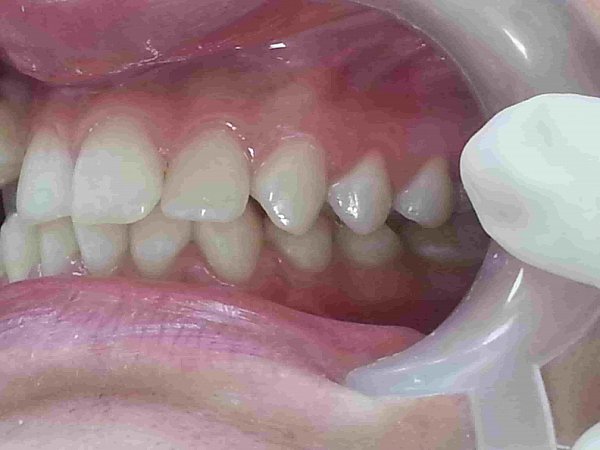

Пациентка 16 лет. Жалобы на неправильное положение зубов, нарушение прикуса.

Ортодонтического лечение проводилось на

Диагноз: Мезиальная окклюзия, тенденция к вертикальной резцовой дизокклюзии, скучное положение зубов.

Фактический срок лечения 25 месяцев